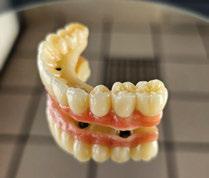

El procedimiento de diseño, impresión, pulido y cementación de aditamentos consume

Figura 34. Rehabilitación superior impresa en resina Bego VarseoSmile TriniQ® lista para atornillar. Se han anulado de la oclusión aquellos implantes que no obtuvieron una estabilidad primaria superior a 35 N/cm2 Figura 31. Escaneado intraoral postcirugía. Figura 32. Rehabilitación recién impresa a través de impresora Varseo XS con resina Bego VarseoSmile TriniQ®. Figura 33. Ajuste pasivo entre aditamentos protésicos y la rehabilitación impresa.

aproximadamente una hora y media. Usamos resina Bego VarseoSmile TriniQ® para puentes definitivos. Aunque en este caso la vamos a usar para confeccionar unas prótesis fijas atornilladas provisionales de larga duración, dado al aumento de dimensión vertical que vamos a realizar a la paciente, de esta forma obtendremos una neuroprogramación de la ATM reinstaurando una Dimensión Vertical apropiada y mejorando la estética facial de la paciente. Excluimos de la carga aquellos implantes que no obtuvieron una estabilidad primaria superior a 35 N/ cm2. El material permite la realización de una carga inmediata en material definitivo en puentes (Figuras 31 a 38).